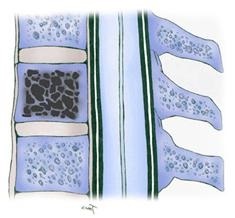

Pe vertebra deja modificate după naștere de-a lungul vieții lor va oferi o varietate de efecte mecanice și fizice care pot contribui la apariția microtrauma constantă și hemoragie a vaselor de sânge subțiri și fragile morfopatologic. Pentru a opri reacțiile de coagulare activat hemoragie organism, inclusiv formarea unei cantități masive de cheaguri de sânge la nivel local. La celulele același timp activate, osteoclastelor, care distrug osul grinzi corpurile vertebrale și promovarea creșterii de noi vase pe locul gol după procesul de recanalizarea de cheaguri de fibrină de sânge. Deci, încet, dar sigur, există o creștere a conglomerat vasculare patologice.

Având în vedere caracteristica a tumorilor plasa nu este greu de imaginat ce a declanșat principalele simptome ale bolii. Aceasta se manifestă pe fundalul dinamicii locale sub forma unei schimbări negative în parametrul corp pathologically format vertebră înălțimea sa cu dezvoltarea și prăbușirea posibilă comprimarea rădăcinilor nervoase adiacente ce se extind sub formă, cum ar fi hemangioame spinării. Dimensiunea tumorii, mai ales în cazul în care este nevoie de o cavitate vertebrală complet, afectează în mod direct clinica si gradul de manifestare a durerii.

încărcare normală devine periculoasă și poate duce la o fractură prin compresie în leziuni ale procesului patologic mai mult de jumătate din corpul vertebral. În cazul în care a fost deja observat violarea integrității vertebrei, compresia substanței măduvei spinării pot manifesta modificări semnificative până tulburările de micțiune, sau tulburările de circulație în funcție de tipul de paralizie.